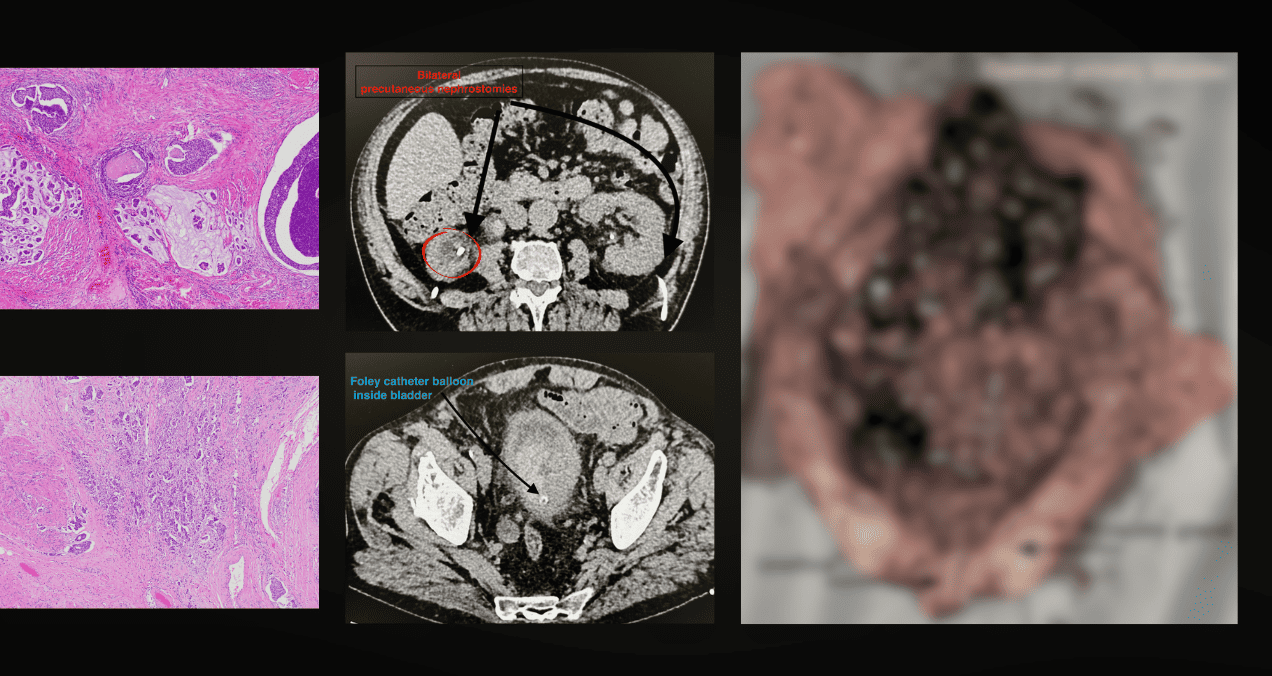

Ante el rápido deterioro clínico, el equipo multidisciplinario optó por una cistoprostatectomía radical de emergencia. Durante la intervención se encontró un tumor urotelial extensamente necrótico que había comprometido casi toda la vejiga, con paredes extremadamente frágiles aunque sin perforación evidente.

El análisis del líquido peritoneal mostró características compatibles con inflamación química más que infecciosa.